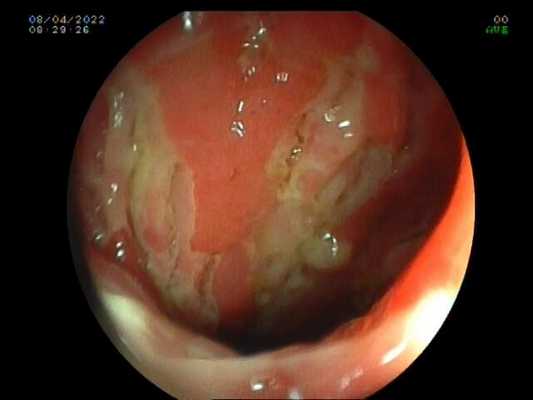

ВРВ пищевода после эпизода кровотечения. Тромбированная вена - тромб белого цвета..